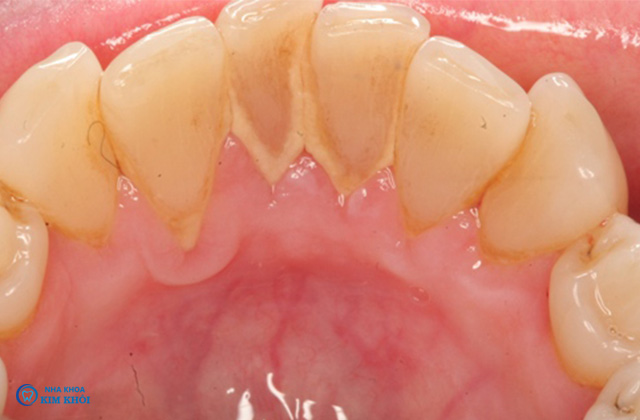

Vôi răng hay cao răng là những mảng bám mảnh vụn thực phẩm còn sót lại sau khi ăn. Đã bị vôi hóa bới vi khuẩn có trong nước bọt muối canxi carbonat và calcium phosphate. Mảng bám thức ăn thường lắng đọng thành lớp dày ở thân răng, nướu có màu trắng đục hoặc vàng nâu mất thẩm mỹ và gây tổn hại nhiều đến răng miệng.

Phá hủy men răng khi mảng bám tích tụ quá nhiều, dày và lâu ngày. Nguy cơ sâu răng càng cao nếu men răng bị tổn thương càng nặng.

Hiện tượng tụt nướu làm lộ chân răng.

Đây là nguyên nhân chính gây ra các bệnh răng miệng. Những bệnh như viêm nha chu, tiêu xương ổ răng, viêm tủy răng ngược dòng. Có thể khiến răng lung lay, rụng răng gây mất thẩm mỹ.